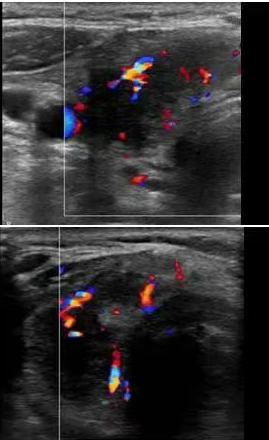

关于甲状腺结节,其就是指在人体的甲状腺部位生成了一定的肿块.该肿块会随着人体吞咽动作的进行而移动,关于这一疾病的出现,可能由多种病因引起,而不同的病因造成的甲状腺结节,可能会呈现出不同的状态 一、(1)低回声、边界不清

(2)结节有血流信号

(3)纵切图像及彩色多普勒图像 二、(1)位患者结节的横向图像:有边缘样但不连续的钙化